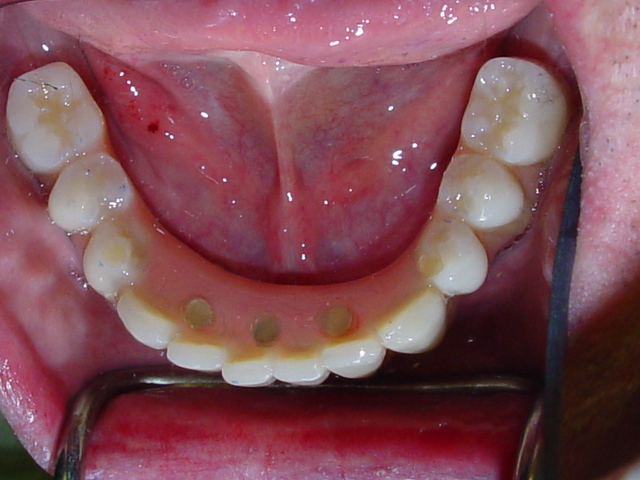

14-full-crowns-precision-denture-implants-makeover-after-8